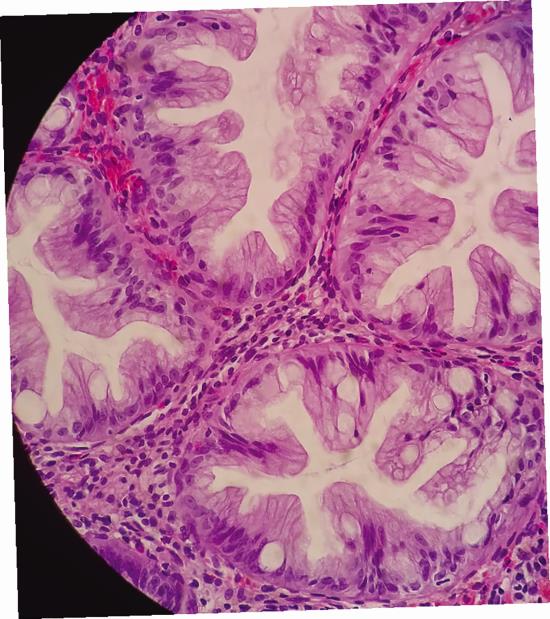

Зубастые цветки доброкачественного гиперпластического полипа.

В то время как папиллярный рак смотрит на нас пустым взглядом героини комиксов, иногда толстая кишка может взорваться под микроскопом целым фейерверком разных цветов. Возможно, вы знаете, что не все полипы, обнаруженные в кишечнике, раковые, есть и доброкачественные. Гиперпластические полипы, непреодолимо ассоциирующиеся (под микроскопом, конечно) с изображением цветущего луга, отмечаются довольно часто, а с возрастом все больше и больше. В учебниках говорится, что их можно найти как минимум у 35 % людей старше 50 лет, вообще не имеющих жалоб, связанных с пищеварением. Из-за цветочного или согласно некоторым представлениям «зубастого» изображения патологически измененных кишечных желез, которые на самом деле невелики, категория полипов, к которой мы их относим, получила название зубчатых полипов, а гиперпластические полипы – самые многочисленные, а также наименее опасные представители группы полипов. Вы знаете термин «апоптоз»? Это процесс плановой гибели клеток, постоянно происходящий в различных частях нашего тела и необходимый для его правильного функционирования. Что ж, процессы умирания, происходящие в кишечных железах, считаются одним из важных факторов развития таких цветов. Это, конечно, определенное упрощение, но кишечные крипты (углубления) – довольно активные места, на их поверхности микротрубочек слизистой оболочки кишечника постоянно образуются новые эпителиальные клетки, которые по мере взросления поднимаются и постепенно отмирают. Считается, что это клеточное «коловращение» нарушается в гиперпластических полипах, отсюда и избыток клеток, которые наслаиваются в такие напоминающие зубчики и цветки формы. Такие вот зубастые цветочки.